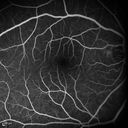

16 year old with incidental finding of retinal AV malformation but vision in the left eye is not as good as the right eye. VA OD: sc20/16 NscJ1+ VA OS: sc20/20-1 NscJ1+